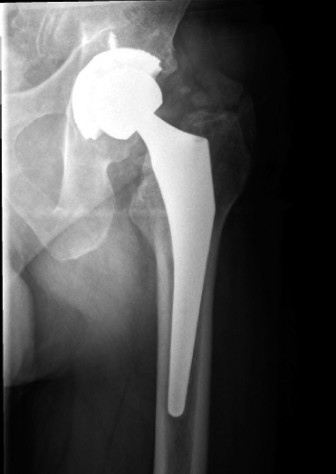

Figure 2: Intraoperative view showing a well-placed acetabular component. Careful attention to posterior component placement and avoidance of overhang or prominent screws is crucial to prevent sciatic nerve impingement. -